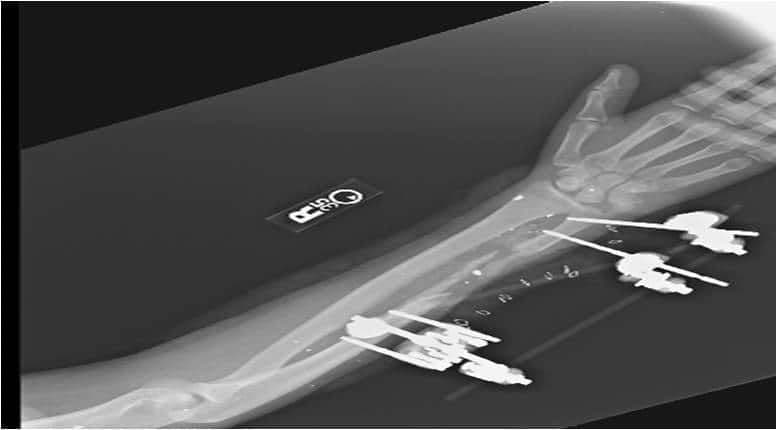

3. див зобр. 15. Передньозадня рентгенограма зовнішнього фіксатора ліктьової кістки. Висловлені тут точки зору належать авторам і не відображають офіційну політику чи позицію Медичного центру армії Брук, Медичного департаменту армії США, Офісу генерального хірурга армії США, Міністерства армії США, Міністерства оборони або уряду США.

Зобр. 15